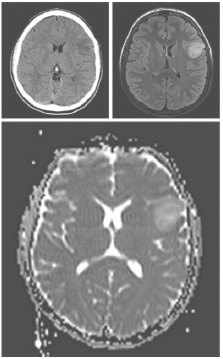

Uma paciente de 45 anos de idade com história de infecção urinária de repetição foi admitida na emergência de um hospital com dor dorsal lancinante. O exame neurológico é normal e a ressonância magnética é mostrada a seguir.

O diagnóstico mais provável para esse caso é:

Um paciente de 41 anos de idade é admitido no

pronto-socorro com história de crise convulsiva

tônico-clônica generalizada. Foi submetido à

ressonância de crânio, como mostra a imagem a

seguir.  O método cirúrgico auxiliar mais apropriado para